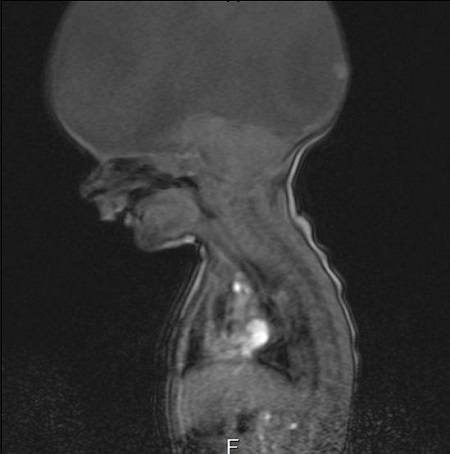

An X-ray of Aaron's brain

As soon as he was born he was rushed to the neo-natal unit. It was then a scan revealed Aaron’s brain had not formed properly. He only had a stem and not a full brain. It was an incredibly emotional moment for mum Emma.